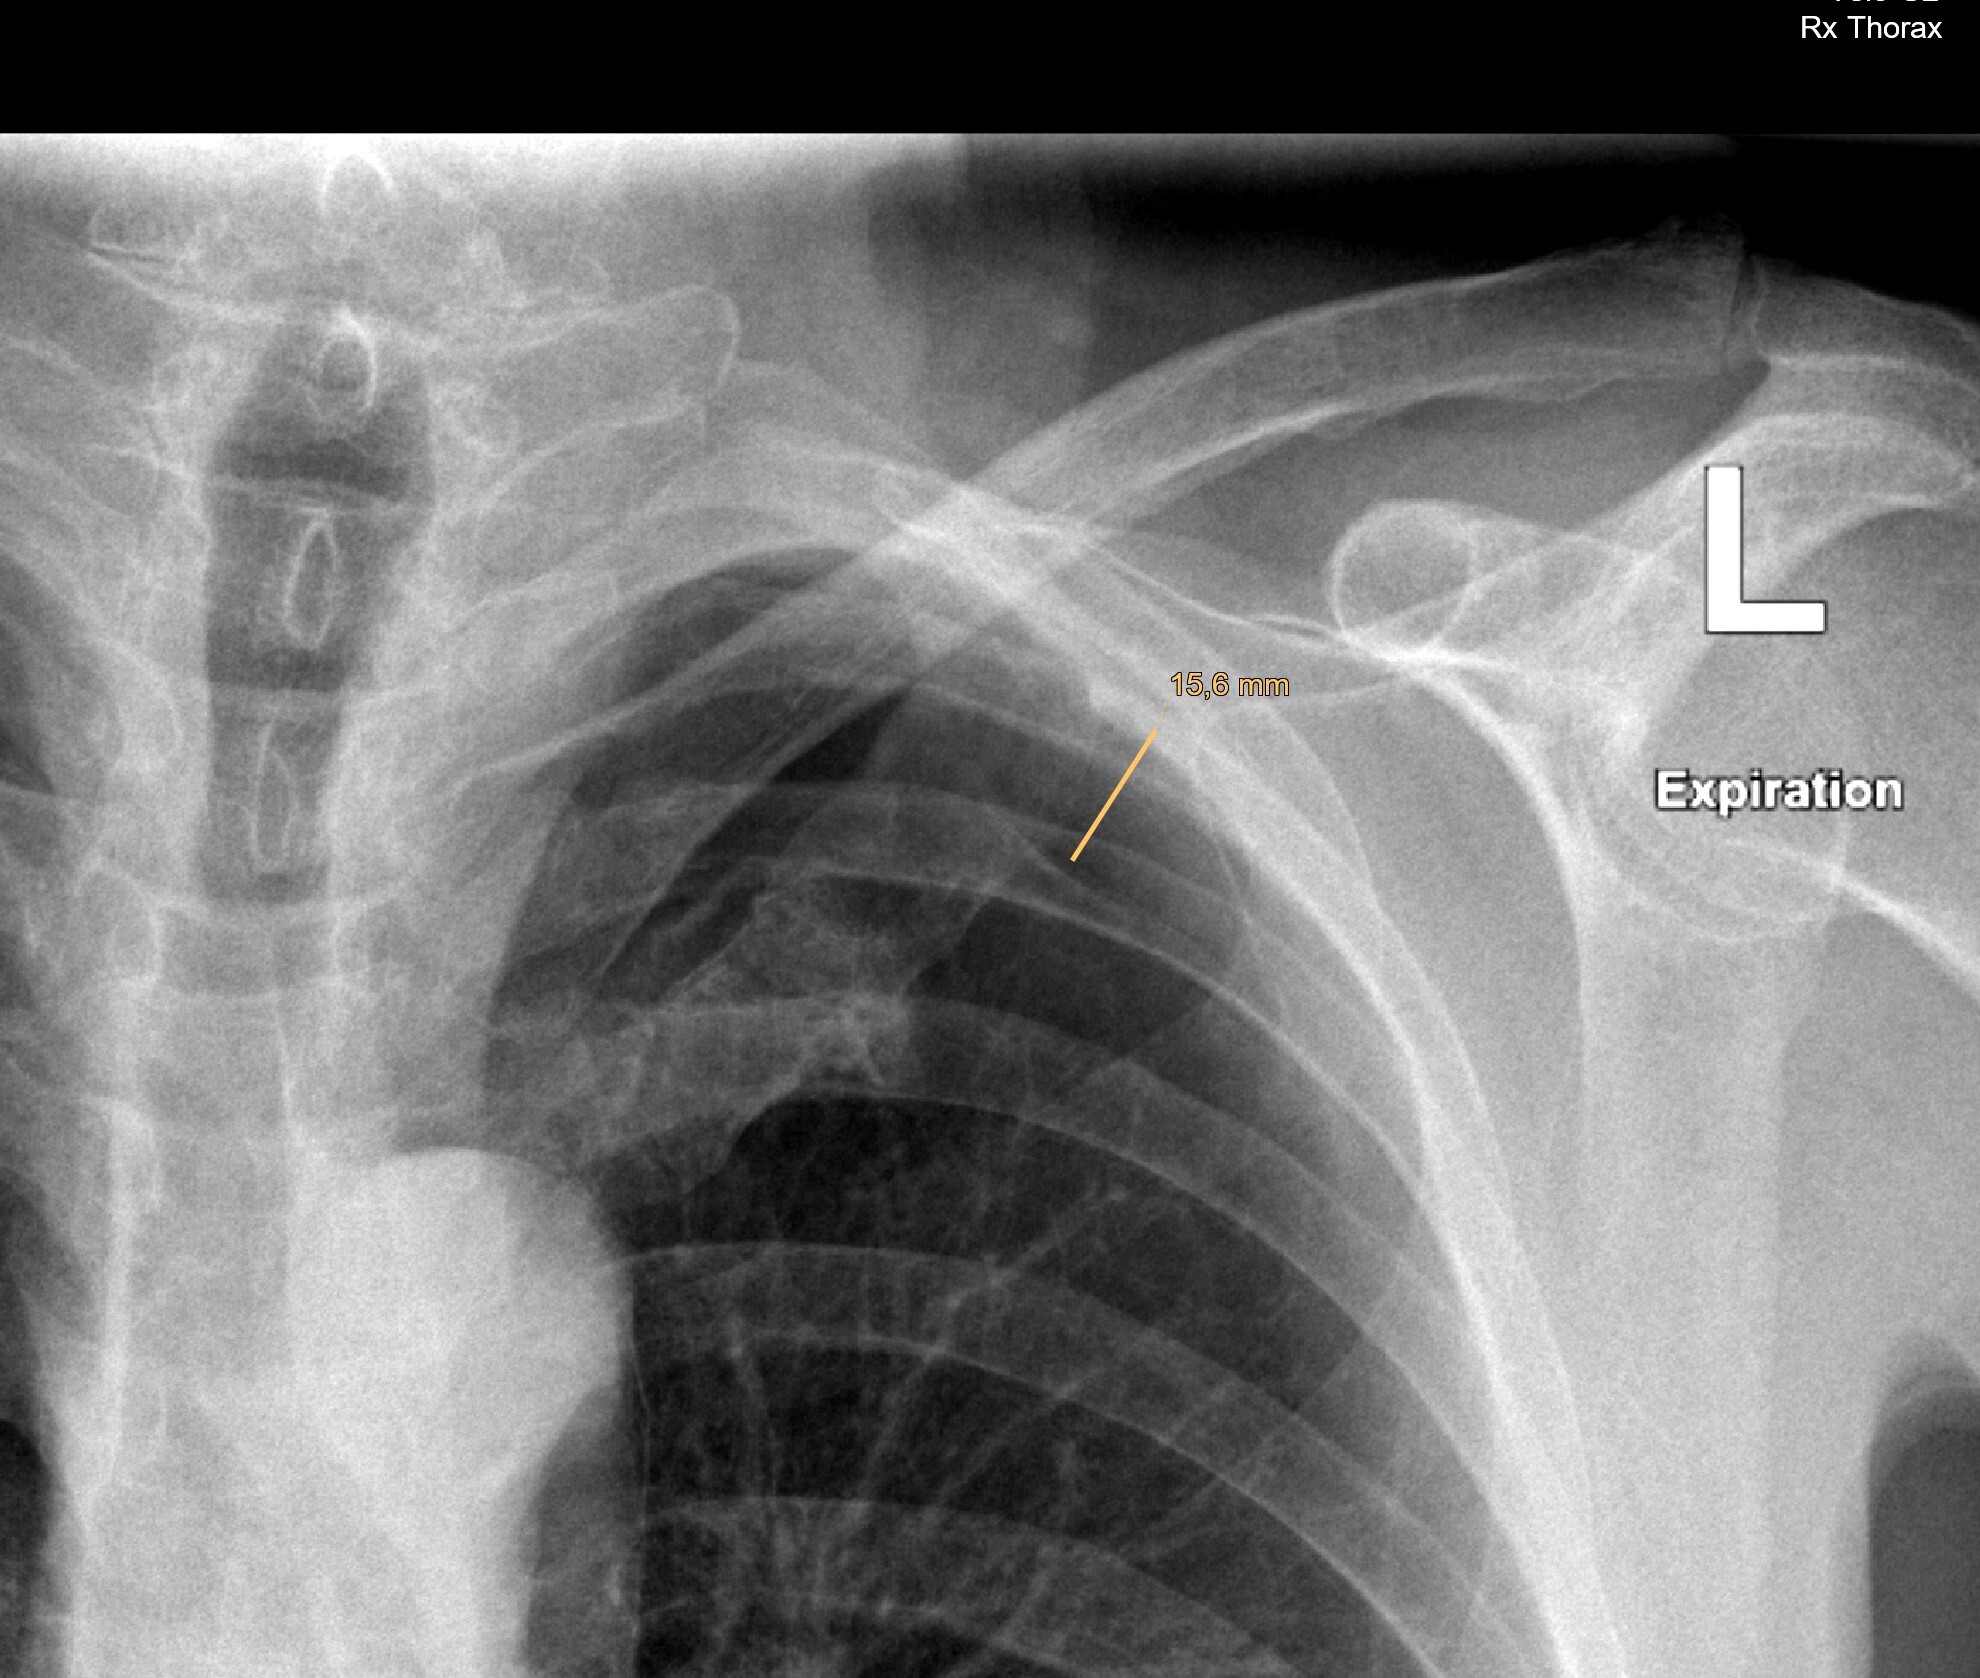

Сегодня мне посчастливилось сделать биопсию лёгкого у мужчины, 68 лет, с подозрением на рак в апикальном сегменте левой нижней доли (на картинках ниже смотрим на правую часть, белое пятно и есть возможное зло). Вроде и образование не шибко маленькое и пункция особых проблем не обещала, но настораживала близость очага к междолевой борозде, которую имелись все шансы повредить, что, статистически, является предпосылкой к пневмотораксу (воздух в плевральной полости):

Через 2 часа сделали контроль рентгеном, пневмоторакс ещё виден, но только апикально т.е. на верхушке лёгкого (тут придётся мне поверить, т.к. я смотрел на спец.мониторе с высоким разрешением):

На контроле ещё через 2 часа (т.е. в целом через 4 часа после пункции) пневмоторакс особо не изменился и даже немного уменьшился, что говорит о его стабильности и небольшом рассасывании: